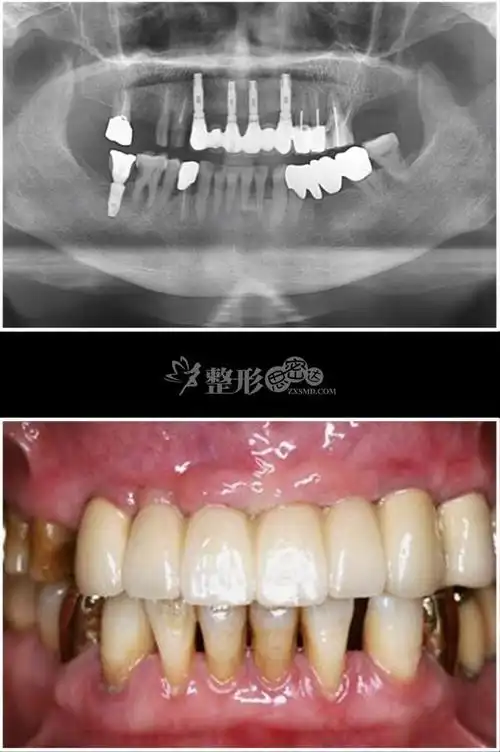

种植牙 3后.jpg